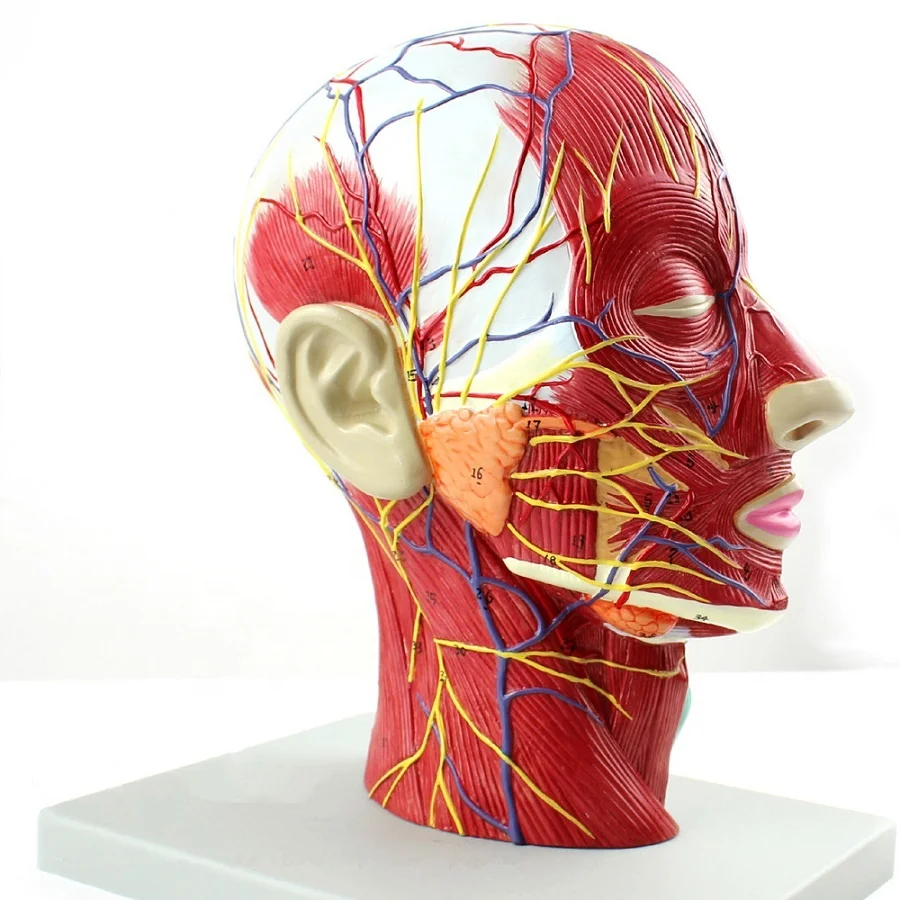

2. Anatomically mimic muscular system with the main superficial arteries, veins and nerves and the area of the neck are demonstrated.

3. 100 positions are displayed.

Size:life size 27*10*20cm